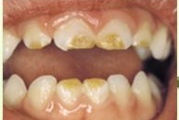

Vali sind huvitav pilt ja me näitame sellega seotud haigust ja sümptomeid